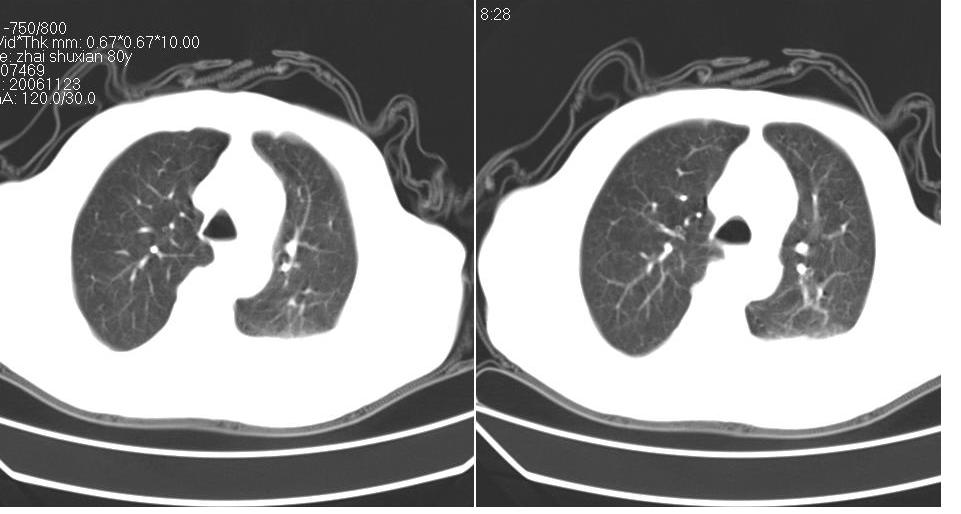

男 80岁,外院病人,有脑梗塞病史,近两个月发热,体温38.5度左右,抗炎后体温正常,药物停有发热。

左肺下叶略萎陷、实变,内可见含气支气管征。左舌叶、中叶亦见少许斑片状高密度区,边界不清。纵隔未见肿大淋巴结影。

考虑:1、肺感染;

2、建议严格抗炎治疗后复查。

左下肺体积缩小,密度增高,见片增密影。边界模糊,见支气管充气像,肺门纵隔无异示,心脏气管左移,左侧胸腔少量积液。考虑肺部感染伴部分肺不张[有脑梗塞病史坠积性肺炎可能]